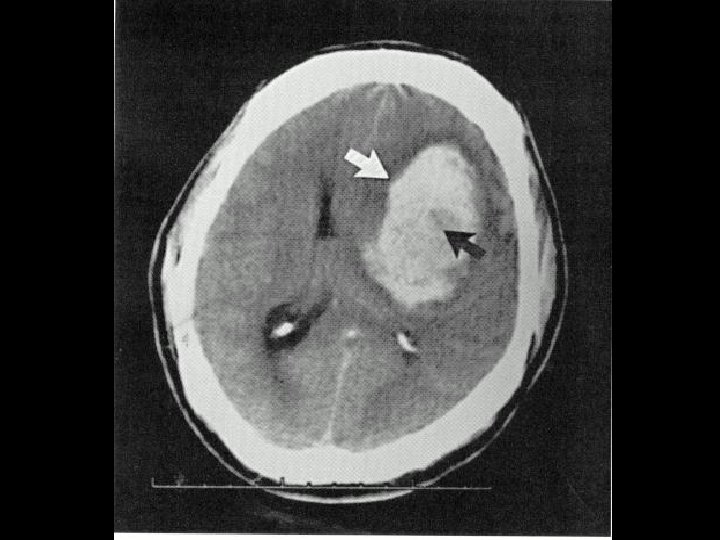

Possible causes of cerebral edema:Cerebral edema Swelling can occur in specific locations or throughout the brain. Prompt intervention matters a lot for faster recovery without causing any damage to the brain. Cerebral edema treatment may involve a combination of medication and surgery.

It may be the removal of a growth or repairing a damaged artery or vein after stroke.In this procedure, a plastic tube is inserted into the skull to drain out the excess fluid. Rectifying the source of swelling. A part of the skull may be removed to reduce intracranial pressure. This may have one of the two objectives.